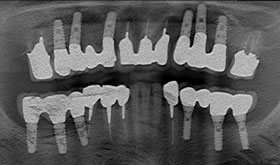

Bさんは数年前に左下の奥歯2本を抜きました。その時の先生は、インプラント治療をやっていなかったので、入れ歯を作りました。Bさんは入れ歯を入れてみて、その違和感にびっくりしました。結局Bさんは、ほとんど入れ歯を使うことなく、はずしたままで過ごしました。なぜなら、入れ歯がなくても反対側の歯で普通に食べることができたのです。Bさんは右側だけで、食べることにしました。

Bさんは数年前に左下の奥歯2本を抜きました。その時の先生は、インプラント治療をやっていなかったので、入れ歯を作りました。Bさんは入れ歯を入れてみて、その違和感にびっくりしました。結局Bさんは、ほとんど入れ歯を使うことなく、はずしたままで過ごしました。なぜなら、入れ歯がなくても反対側の歯で普通に食べることができたのです。Bさんは右側だけで、食べることにしました。

Bさんの右側だけでの食事が数年続いた時、異変がおこりました。右側だけの食事のせいで右の奥歯が悲鳴をあげたのです。Bさんは右の奥歯は1本失うことになりました。

Bさんの右側だけでの食事が数年続いた時、異変がおこりました。右側だけの食事のせいで右の奥歯が悲鳴をあげたのです。Bさんは右の奥歯は1本失うことになりました。

Bさんはインプラント治療を選択することにし、私のところにきました。

右に1本、左に2本のインプラントを入れ、Bさんは破壊の連鎖から抜け出すことができました。